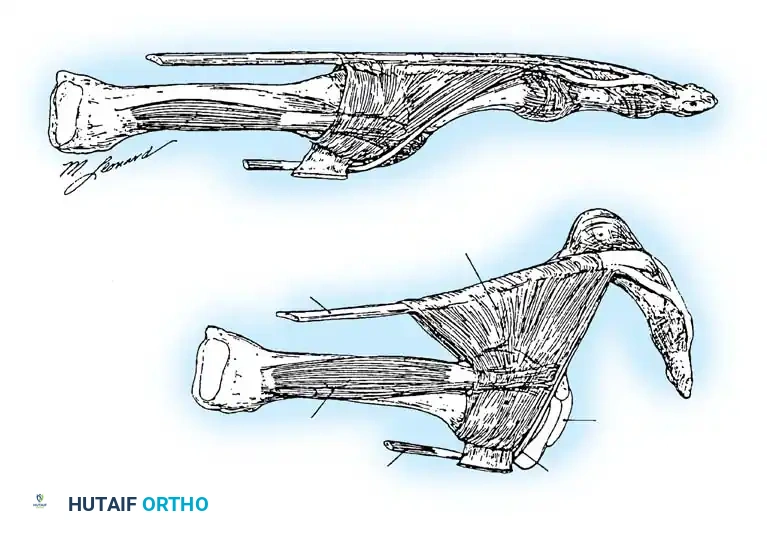

The Flexor-to-Extensor Transfer (Girdlestone-Taylor Procedure)

Originally described for flexible hammer toes, the transfer of the flexor digitorum longus (FDL) to the extensor mechanism is exceptionally effective at providing dynamic plantarflexion stability to an incompetent MTP joint. By rerouting the FDL dorsally, the procedure converts a flexor of the distal interphalangeal (DIP) joint into a dynamic plantar flexor of the MTP joint.

5. Dorsal Routing and Fixation

* By sharp dissection, identify the trailing edge of each lateral band of the extensor mechanism while the skin is retracted, including the dorsal hood aponeurosis, to prepare for the routing of the split flexor tendon slips.

* Using a curved hemostat, create a tunnel passing from the dorsal incision, around the medial and lateral borders of the proximal phalanx, to the proximal plantar incision.

* Grasp the respective slips of the split FDL tendon and pull them dorsally. The slips should embrace the proximal phalanx like a sling.